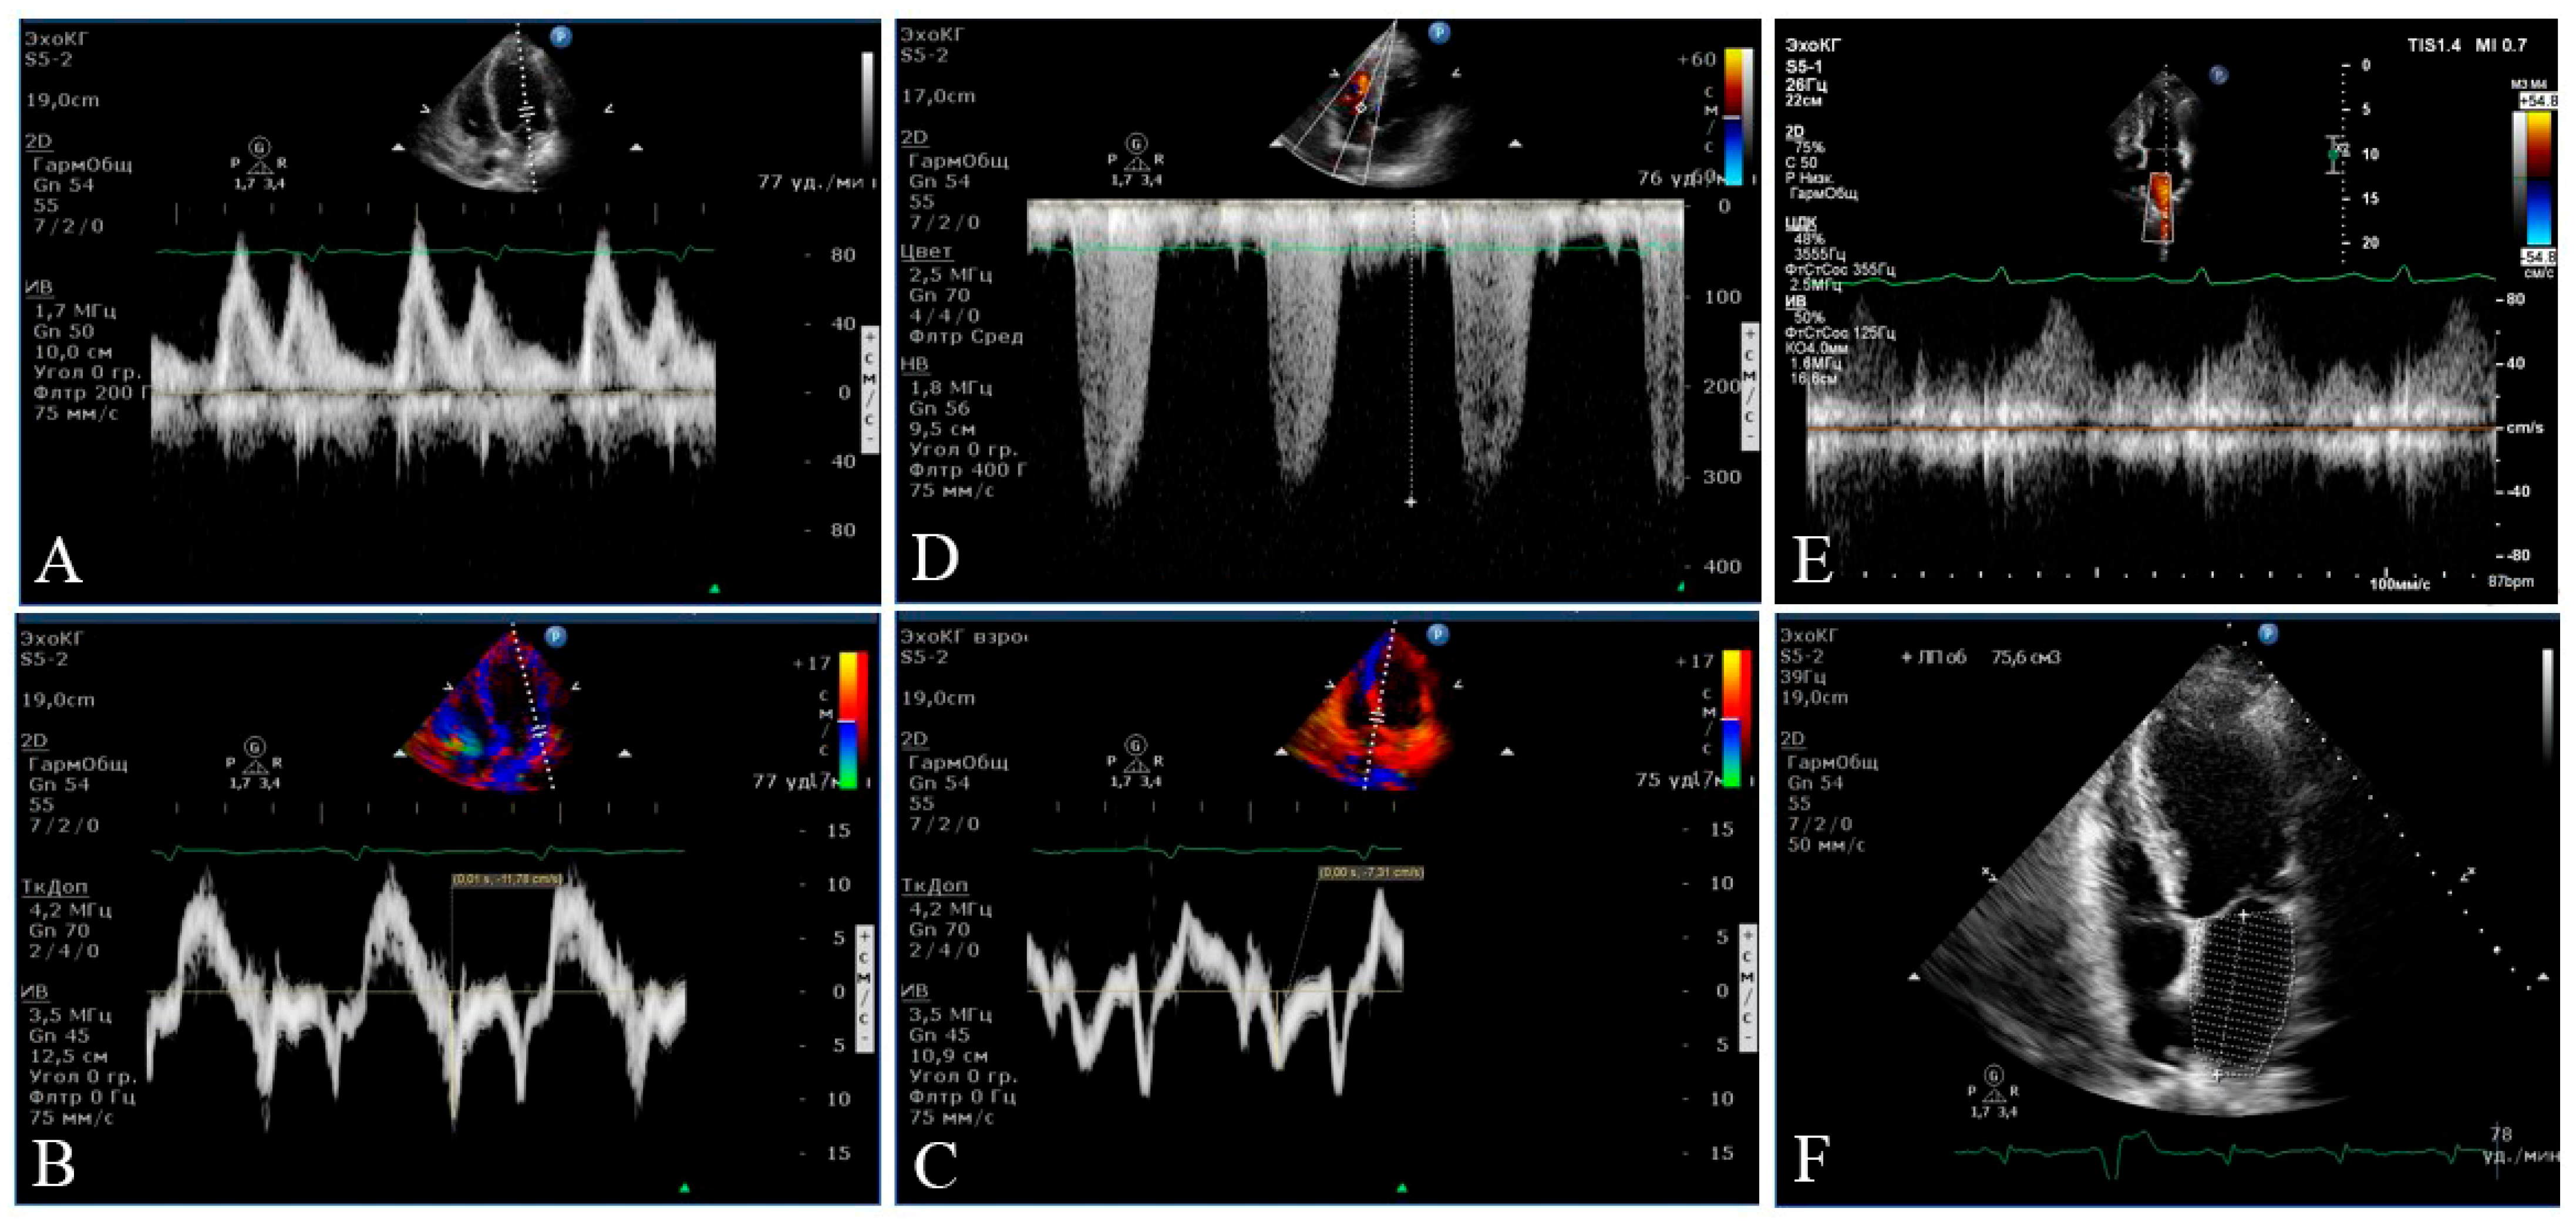

2.3. Instrumental Methods